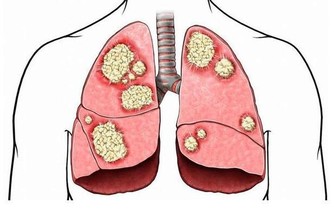

*****4.提高免疫力*****

德國精神病研究所的睡眠專家發現,中午1點是人在白天一個明顯的睡眠高峰。這時睡個短覺,可有效刺激體內淋巴細胞,增強免疫細胞活躍性。